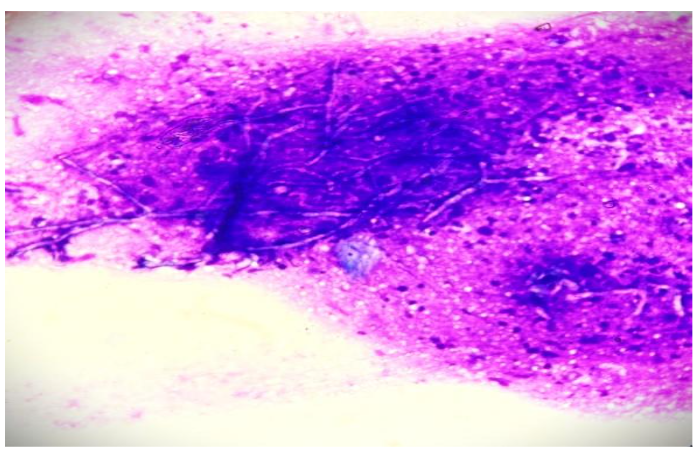

PAS Stain in cytology smears also confirmed the same. Excision biopsy was done and histopathology sections showed an unremarkable epidermis with deep dermis showing organised collections of neutrophils with necrotic centre and multiple septate fungal hyphae with acute angle branching. Spores were also noted. PAS and GMS staining was done and confirmed the presence of fungal elements.

Narrow septate hyphae with acute-angle branching is seen in tissue sections of our case, particularly when special stains are used (PAS and GMS). In our case, cytological examination is pivotal in identifying Aspergillus species, followed by biopsy with fungal stains confirmed the diagnosis.